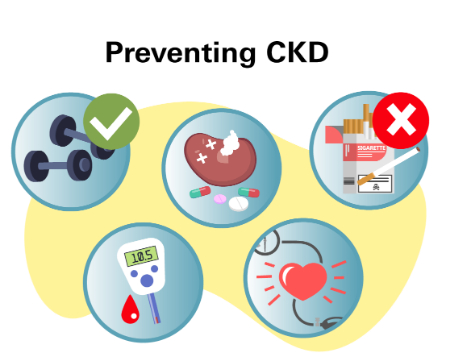

تاری، ابهام در دید و دو بینی از علائم بیماری های چشمی است پیشگیری از بیماری های چشمبا رعایت نکات زیر از ابتلا به بیماری های چشم محافظت کنید:1- میزان گلوکوز خونتان را مدیریت کنید.بهترین کاری که می توانید در راستای محافظت از چشمانتان انجام دهید این است که قند خونتان را در سطح نرمال یا نزدیک به نرمال نگه دارید و از این طریق از عوارض چشمی دیابت در امان بمانید. دو یا […]